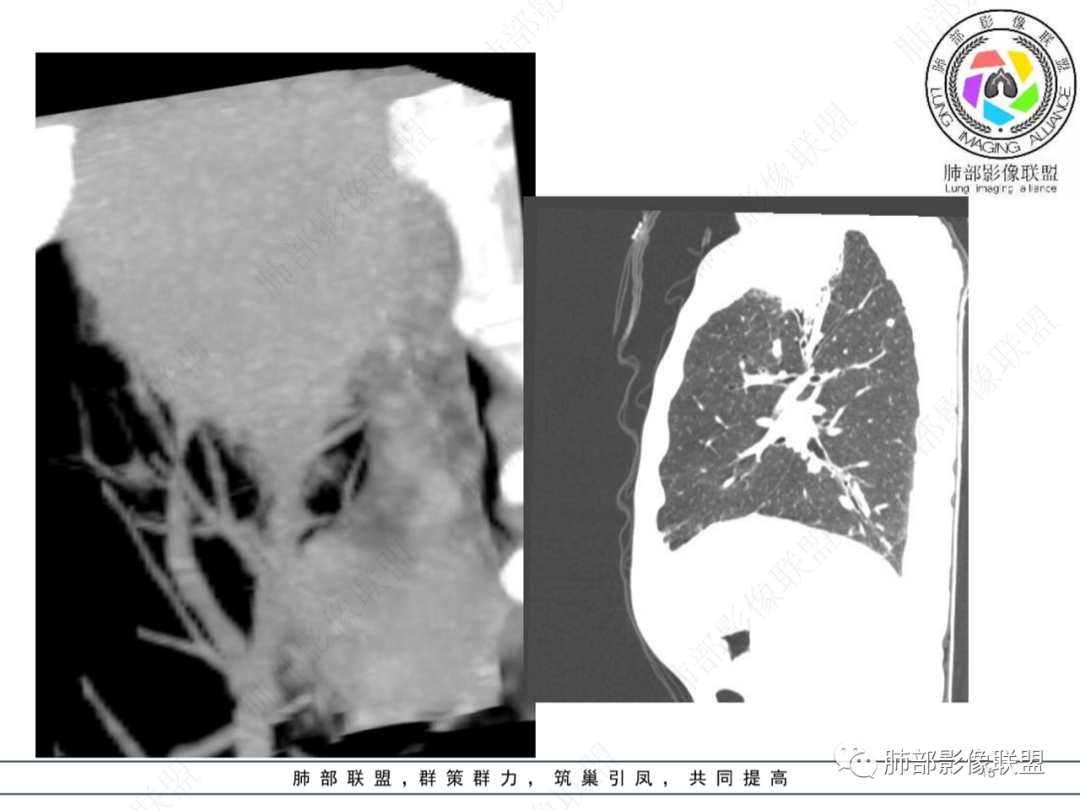

主病灶在右上叶尖段、前段纵隔旁,紧贴胸膜

楔形、边缘膨隆,附近见斑片状、网格状高密度影

支气管近端堵塞,可惜显示的不一定全面

支气管壁还是弥漫增厚

中央坏死明确

如果更薄层一些就好

整体内壁偏清楚,似乎有些地方欠清,不知道是否厚层所致

整体而言:远侧、内侧壁厚

坏死明显,这类膨隆就不支持生长速度不一致所致,而支持坏死朝周围的压力导致边缘的膨隆

这里倒是符合血管的压迫

与胸膜的关系?分界还算清楚

符合炎性的地方:整体形态,可惜重建的图太少

坏死内壁光滑、周围炎性改变

患者有高血压、脑梗死、肾结石病史,因左胸痛不适入院,伴高热,血常规示白细胞、中性粒细胞高。胸部CT示右肺上叶肿块影,边缘模糊影,内可见低密度坏死,边界清楚,一月后出现气液平面,周围渗出,治疗2周复查液平及周围炎症吸收,肿块未见明显吸收。

考虑肿瘤?右肺上叶高密度影,边缘模糊,侵及纵隔及胸廓入口,病灶密度不均匀,部分支气管截断,增强后不均匀强化,内可见较大范围坏死,纵隔多发肿大淋巴结不均匀强化。肺上沟瘤不能排除。